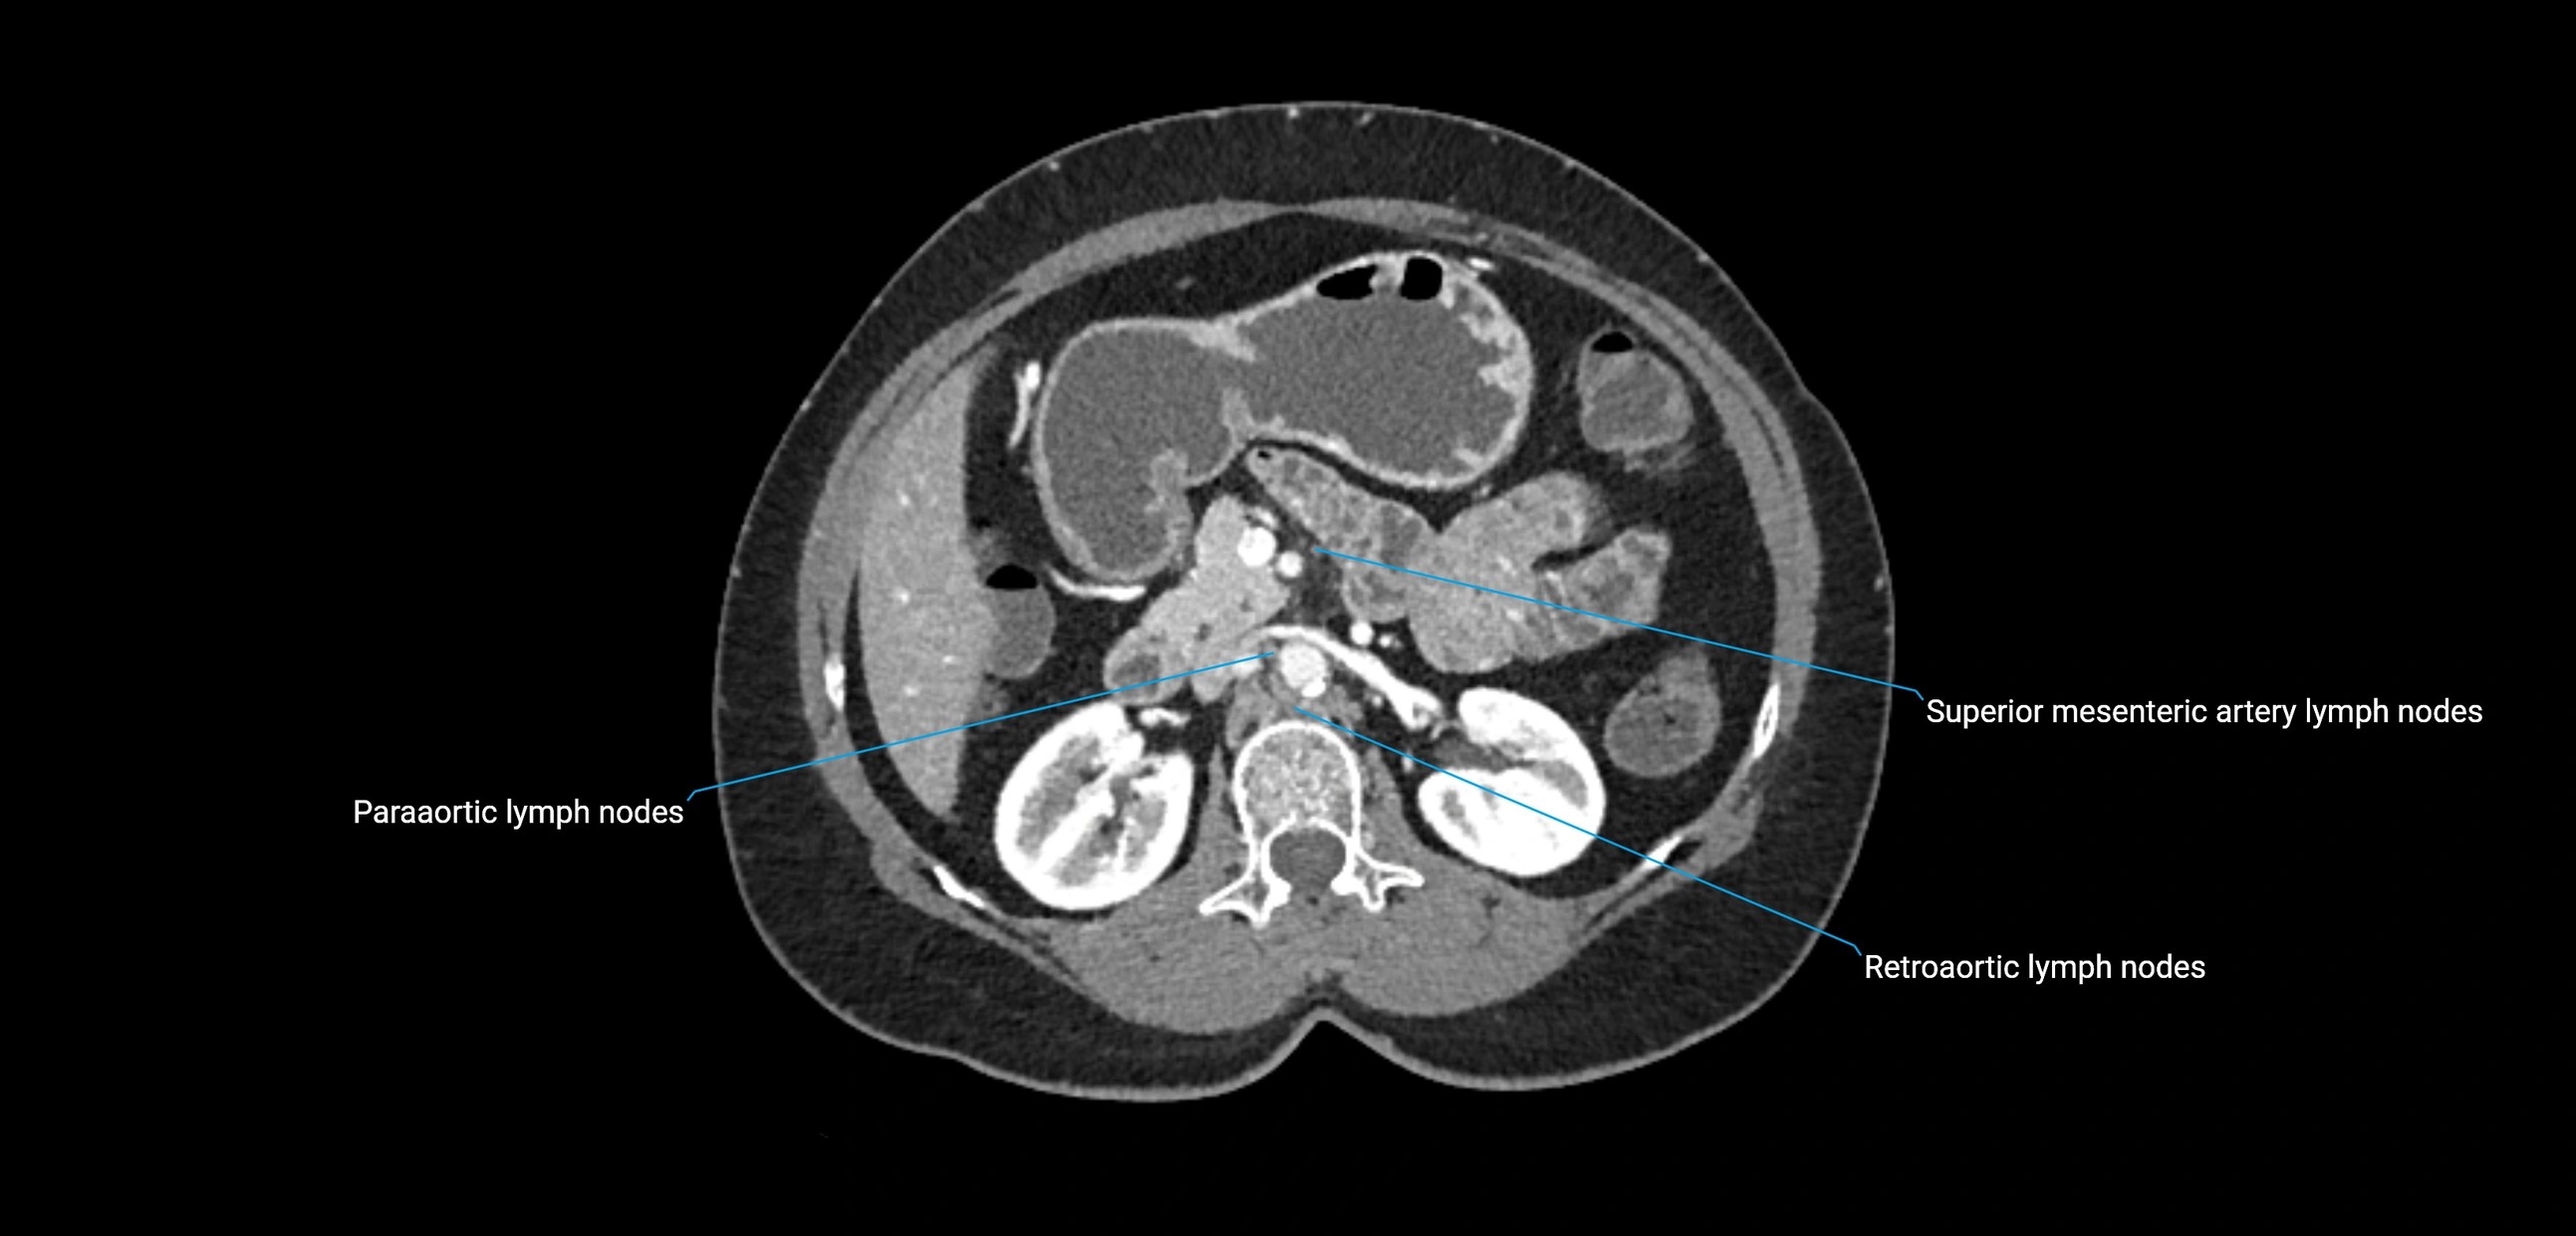

CT image

image